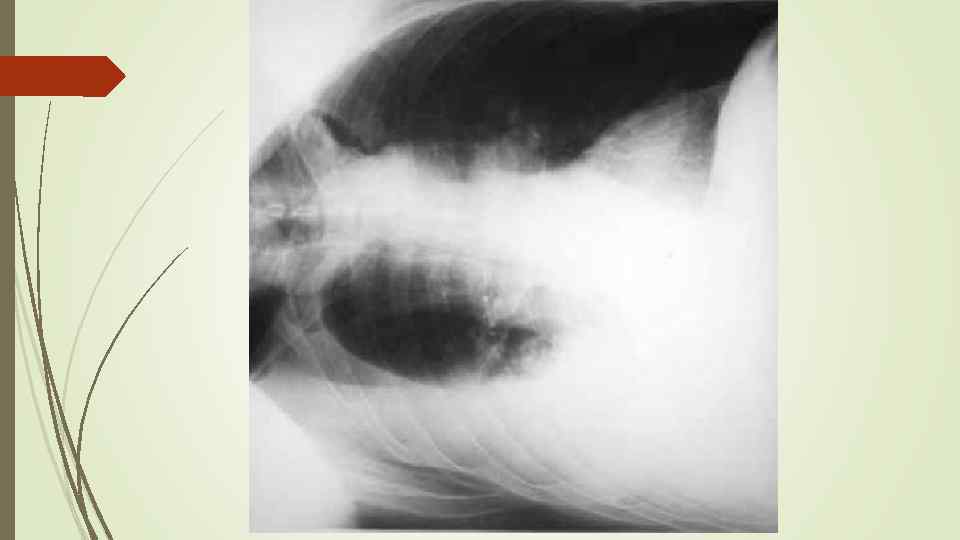

Плевральный выпот Скопление жидкости в плевральной полости (исключение гемоторакс, хилоторакс, пиоторакс) Транссудат Экссудат Плеврит

Плевральный выпот Скопление жидкости в плевральной полости (исключение гемоторакс, хилоторакс, пиоторакс) Транссудат Экссудат Плеврит

Осумкованные плевриты: а) пристеночные (паракостальные) осумкования, прилежащие широким основанием к поверхности ребер; б) верхушечные (апикальные) осумкования; в) диафрагмальные (базальные) осумкования, расположенные между основанием легкого и диафрагмой; г) междолевые (интерлобарные) осумкования, расположеные между долями легких; д) парамедиастинальные осумкования, расположенные в заворотах парамедиастинальной плевры.

Осумкованные плевриты: а) пристеночные (паракостальные) осумкования, прилежащие широким основанием к поверхности ребер; б) верхушечные (апикальные) осумкования; в) диафрагмальные (базальные) осумкования, расположенные между основанием легкого и диафрагмой; г) междолевые (интерлобарные) осумкования, расположеные между долями легких; д) парамедиастинальные осумкования, расположенные в заворотах парамедиастинальной плевры.